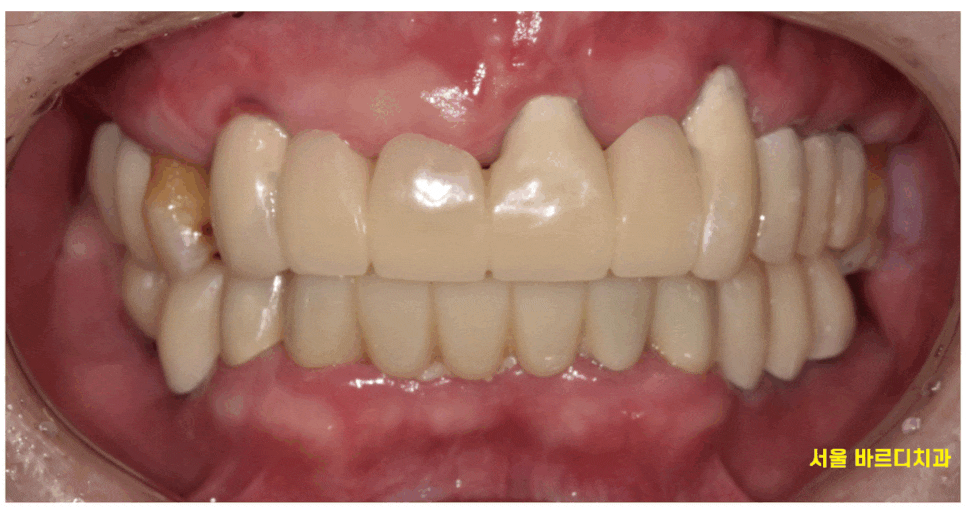

전반적인 어금니 상실로 내원해주신 환자분입니다.

딱 보기에도 제 기능을 하는 어금니가

몇개 없어보입니다.

23.08.17

큰 어금니는 다 뽑히고

작은 어금니 1지점씩만 닿고 있습니다.

양쪽 1개씩 물리는 것으로

그동안 식사를 하셨다해요.